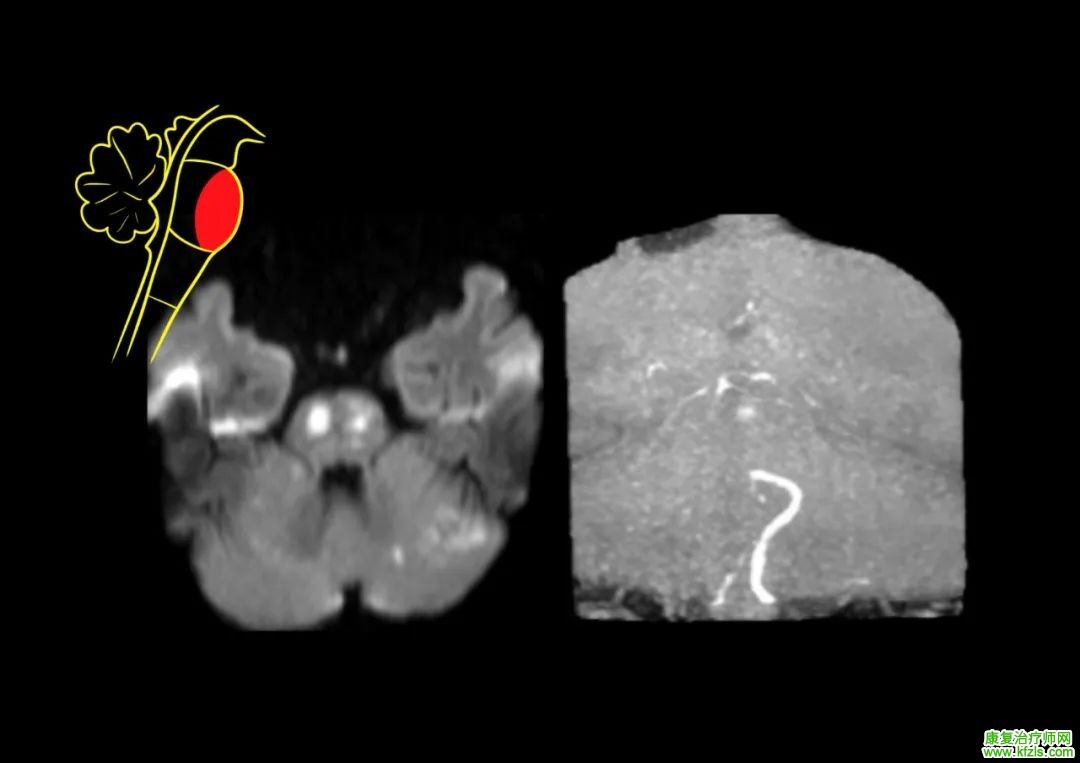

2)延髓旁正中综合征(Dejerine syndrome):

病变位于延髓中腹侧,为椎动脉和基底动脉旁中央支梗死所致。表现为:① 病灶侧舌肌瘫痪及萎缩(舌下神经损害);② 对侧肢体中枢性瘫痪(锥体束损害);③ 对侧肢体深感觉障碍(内侧丘系损害)。

脑干梗死

延髓中部综合征图源:《Duus 神经系统疾病定位诊断学》第 8 版

延髓旁正中综合征核磁表现

图源:参考文献 / 徐桂兴手绘